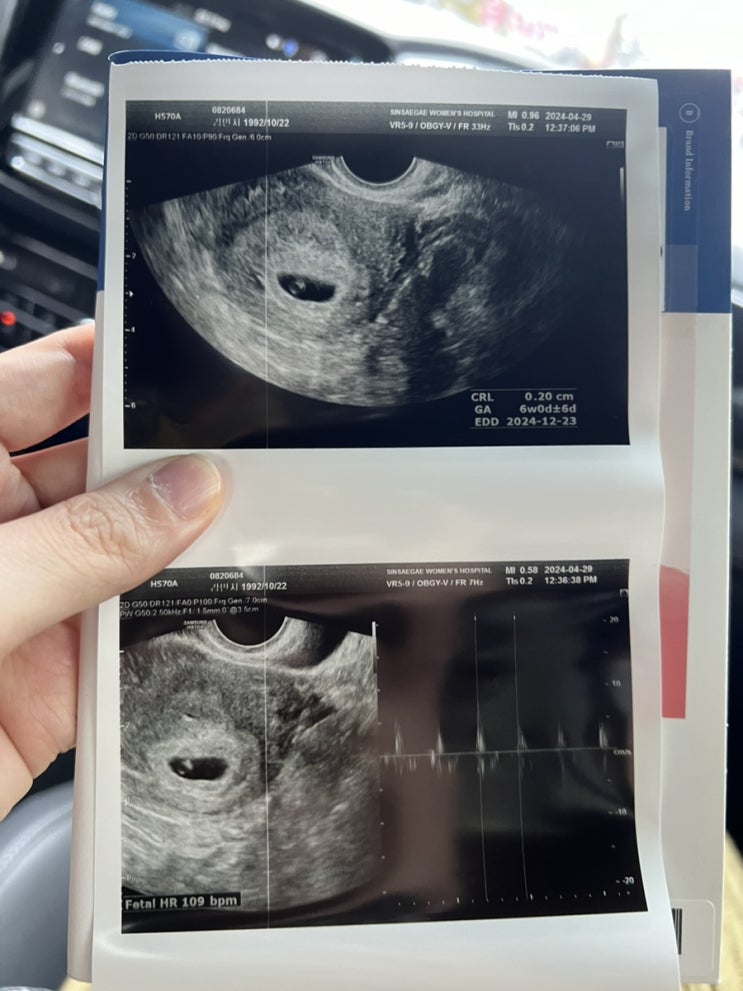

까꿍 하우스 봐찌롱

드디어 까꿍이 집 구경 성공 2주뒤엔 심장소리 들으러 가야지 까꿍이 집 작고 귀엽고 소중해❣️

까꿍이 심장소리❣️

일주일만에 많이커따~~ 심장 소리 못들을줄 알았는데 들었따아 근데 넘 이르고 작아서 잘 안들림 ㅠㅠ 담주...